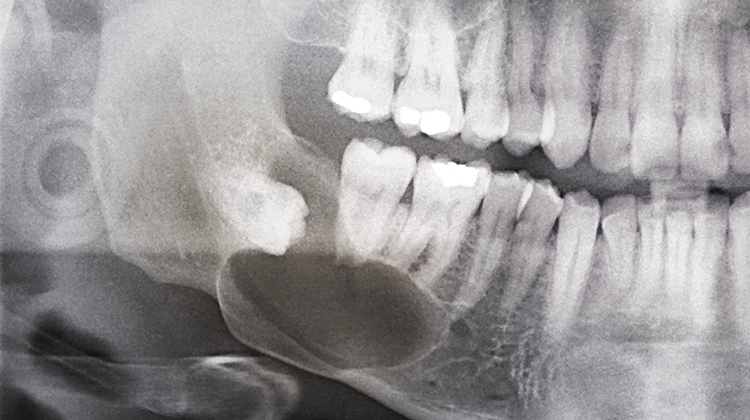

- 사랑니가 겉으로 보이지 않는 경우

- 사랑니가 매복되어 있는 경우에는 많은 경우는 아니지만, 치아를 둘러싸고 있는 치배(치아주머니)에 물이 차서 물혹이 되거나 세포가 변형되어 사랑니 주변 뼈를 점점 흡수할 수도 있습니다.